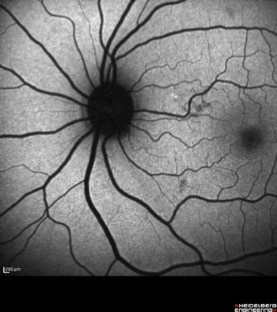

Fig. 1

Fig. 2

Fig. 3

Fig. 4

Fig. 5